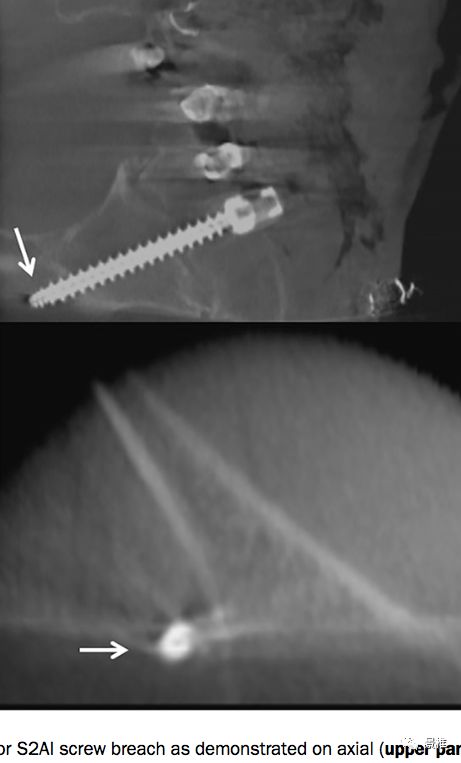

这个技术虽然比较好掌握,但还是会误穿出去(brench),有损伤血管的风险。因此在学习早期,钉道制备过程中务必透视定位。

术中C臂头尾侧倾斜20°-30°,左右斜45°透视,确保钉道在泪滴内。注意示意图中球管的位置,不要摆反了。辐射量也小一些 骨科手术C臂透视防护指南

正位片透视钉道在坐骨切迹上方。